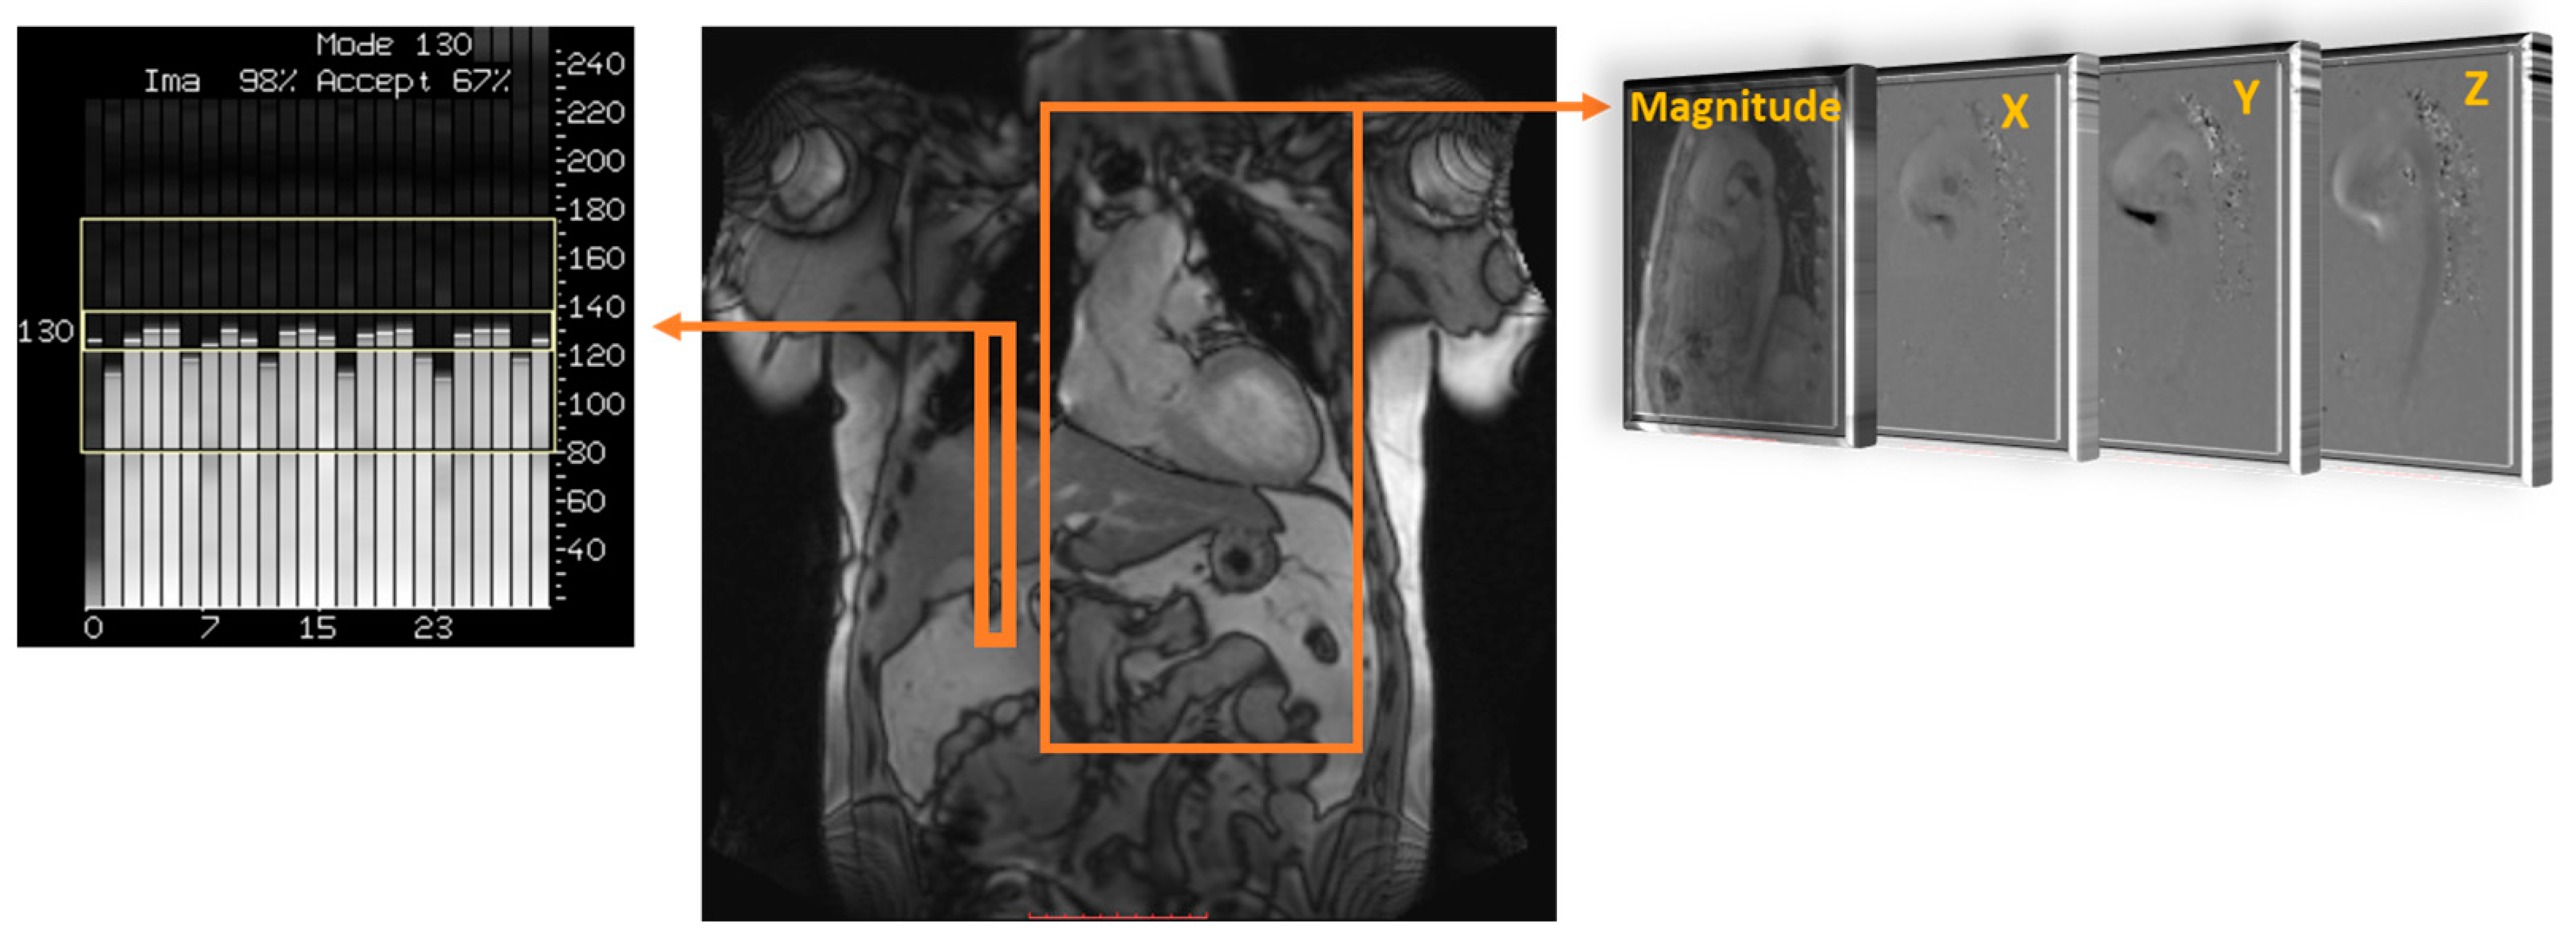

2. Cardiovascular 4D-Flow